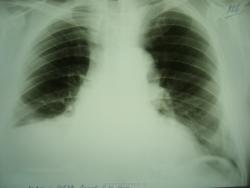

Женщина обратилась с жалобами по поводу кашля и температуры, которая поднимается до38 град. Был сделан снимок в двух проекциях.

Хочется спросить уважаемых коллег: "Есть ли там плевральный выпот"?

Массивное затемнение "вне анатомических границ", чаще всего дает выпот.

И слева, кажется, тоже.Выпот, даже не сомневайтесь.Причем "добрый"( в смысле, жидкости много).

Правосторонний средний гидроторакс. Позвонки одинаковой высоты.

Коллеги! А на ателектаз нижней и средней долей совсем не похоже?

Такой ателектаз средостение хорошенько бы потянул.

Потянул-бы, если-бы выпота справа не было. А так плюс - на минус - средостение-то на месте, при значительном выпоте справа.

Стоит подумать над версией предложенной коллегой lupan